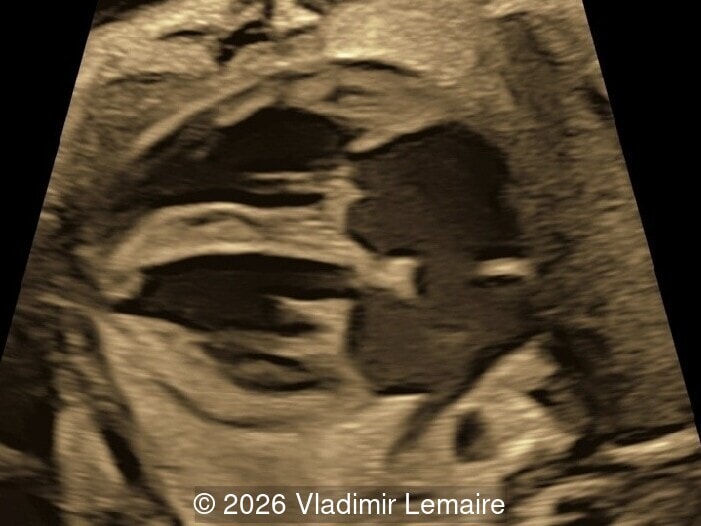

Sagittal image of the fetal head

Image 8 Sagittal image of the fetal head